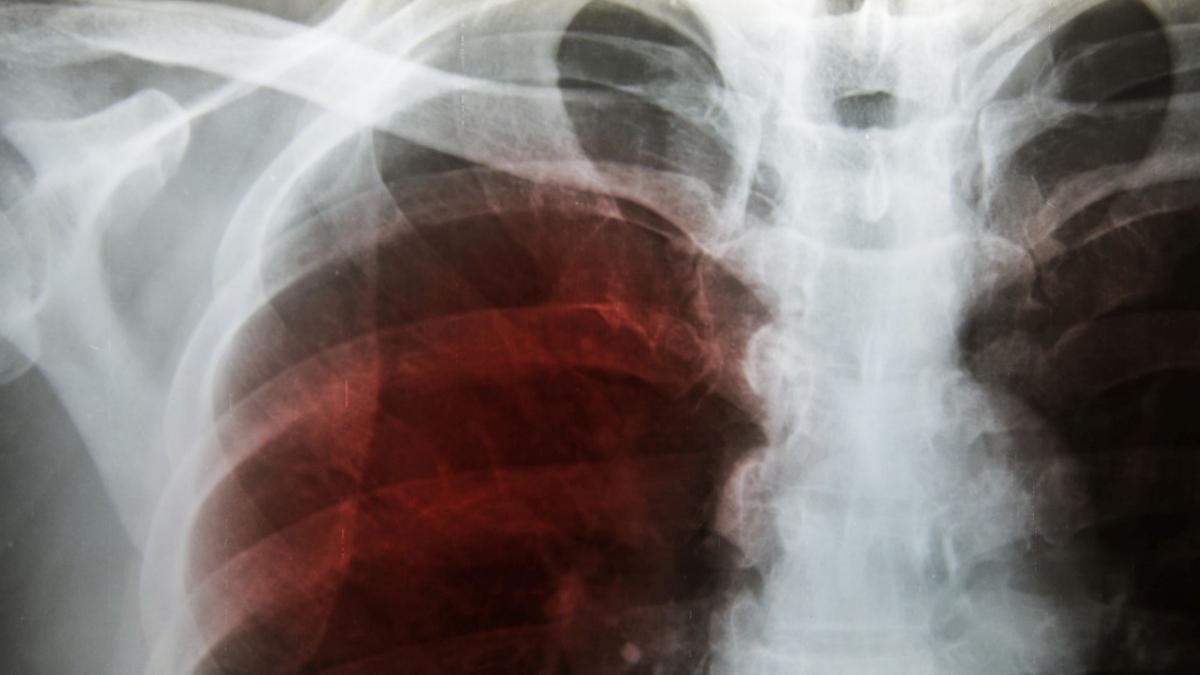

Come riportato nel sito ufficiale dell’Istituto Superiore di Sanità, “con il termine polmonite si indica lo stato di infiammazione del tessuto di uno o di entrambi i polmoni. È comunemente causata da un’infezione batterica ma può essere provocata anche da una infezione virale, fungina o dall’aspirazione di un corpo estraneo”.

Quando questi microrganismi raggiungono i polmoni e li infettano, accade che gli alveoli, ovvero le componenti più piccole dell’”albero respiratorio”, si infiammano riempiendosi di pus e compromettendo, in tal modo, la capacità respiratoria.

Quando si parla di polmonite bilaterale, come nel caso del Pontefice, si intende che entrambi i polmoni sono stati colpiti.